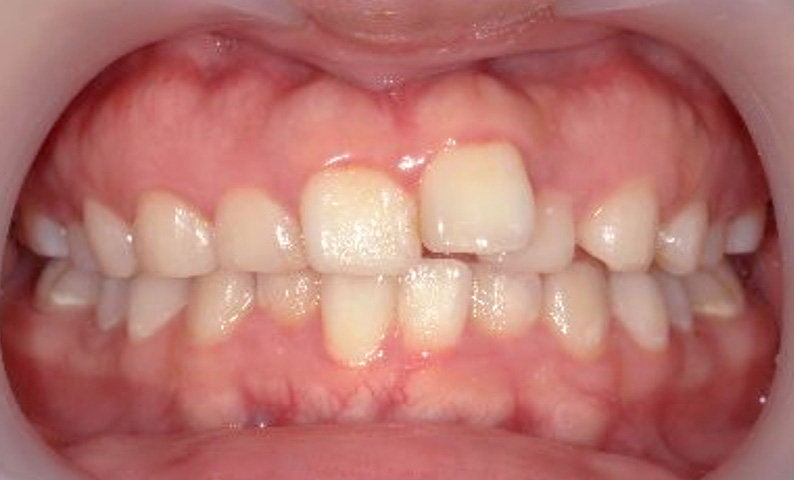

症例_011 上顎だけの部分矯正

治療期間:7ヶ月金額:30万円+税女性八重歯上の前歯だけ

| Before | After |